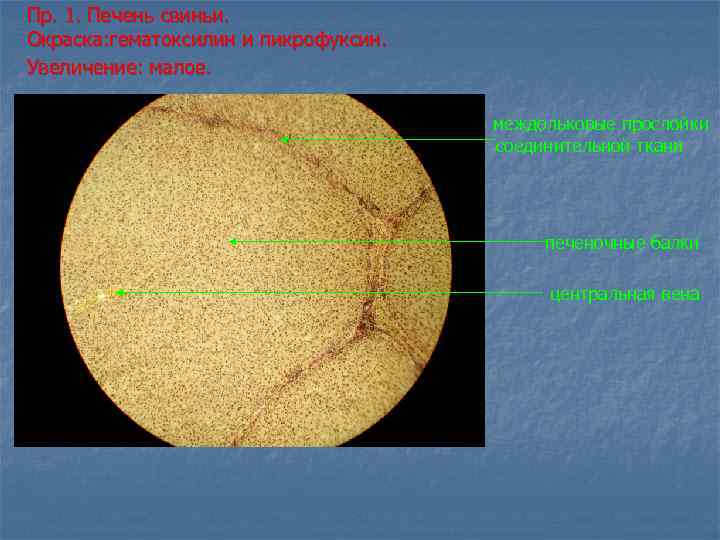

Пр. 1. Печень свиньи. Окраска: гематоксилин и пикрофуксин. Увеличение: малое. междольковые прослойки соединительной ткани печеночные балки центральная вена